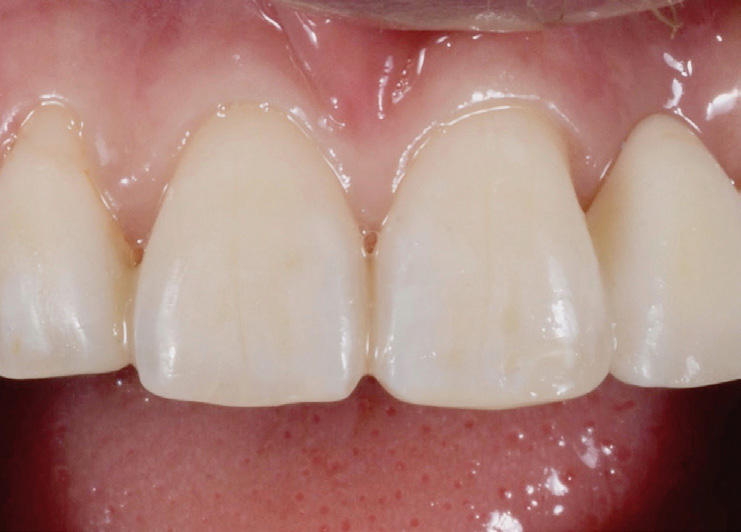

Restoration in place after final clean-up.

Final situation.